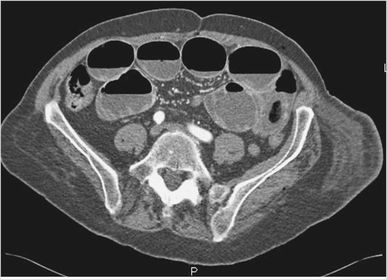

ISQUEMIA MESENTÉRICA

OBSTRUCCIÓN DEL INTESTINO DELGADO

PSEUDOQUISTES PANCREATICOS

VÓLVULO CECAL